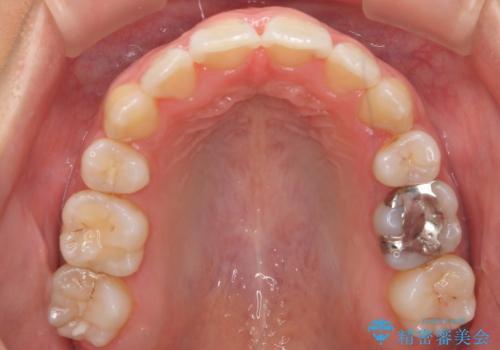

- 20代女性

- 矯正装置

- 審美装置

- 治療計画

- 前歯のがたつきと正中のずれを主訴に来院。

小臼歯を4本抜歯しています。